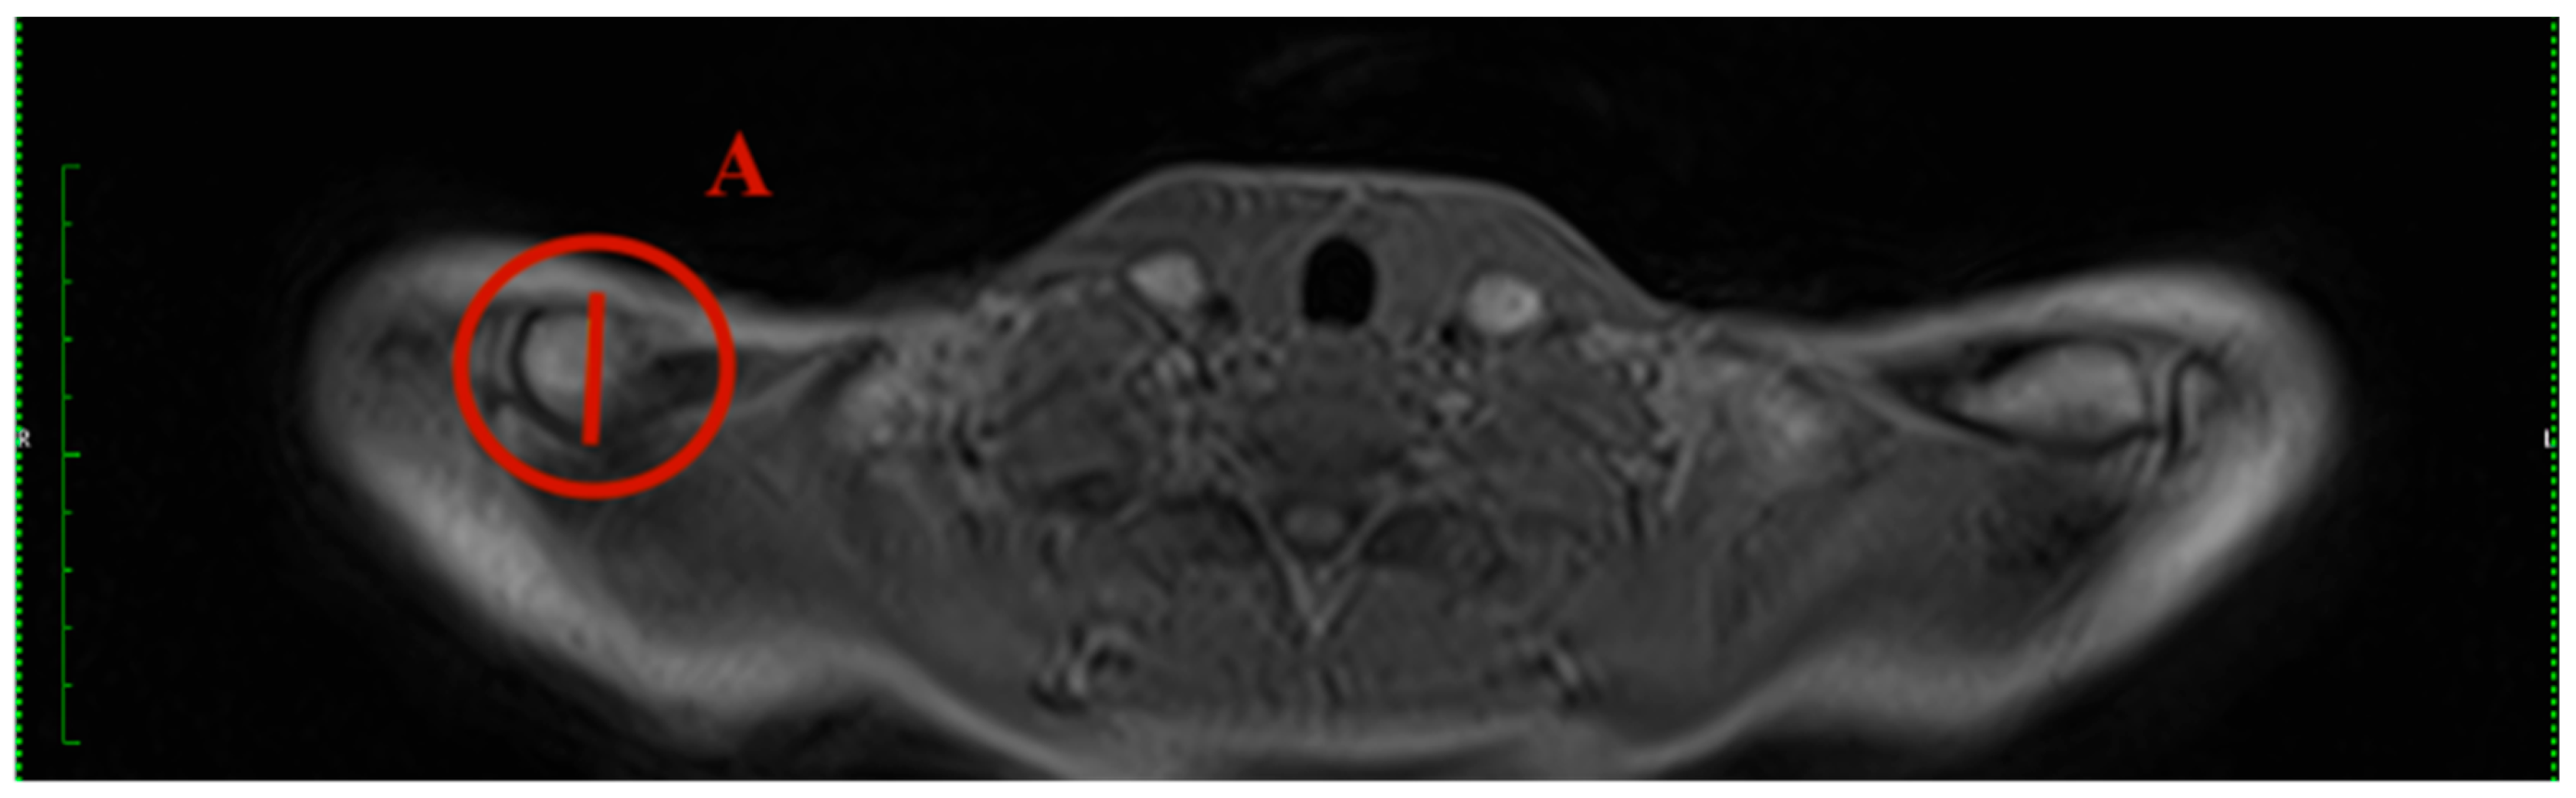

- Clavicular angle: The clavicular angle was measured by the plug-in after two tangents were drawn. One aligns at the articular surface of the clavicular end of the sternoclavicular joint, and the other one at the cranial border of the medial end of the clavicle (Figure 2).